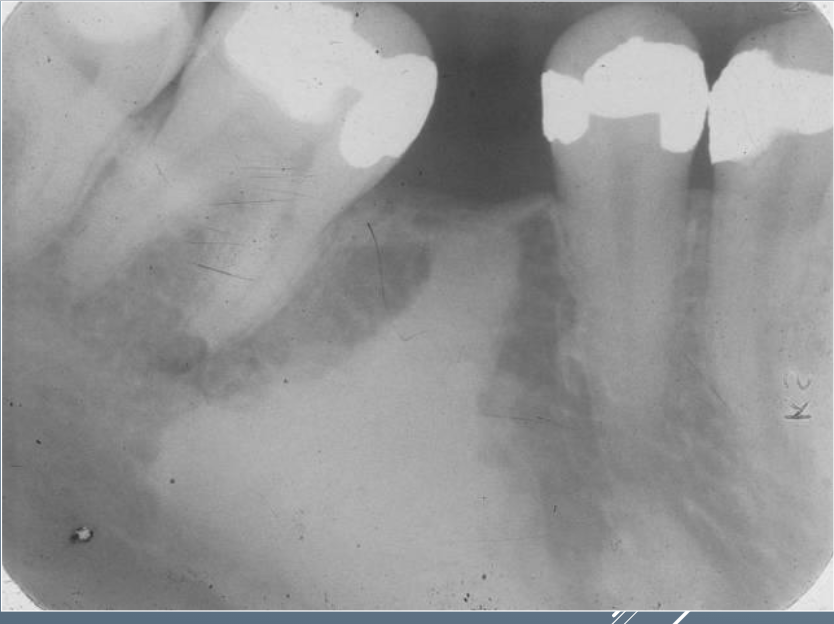

Q

What’s this?

A

CONDENSING OSTEITIS

CHRONIC FOCAL SCLEROSING OSTEOMYELITIS